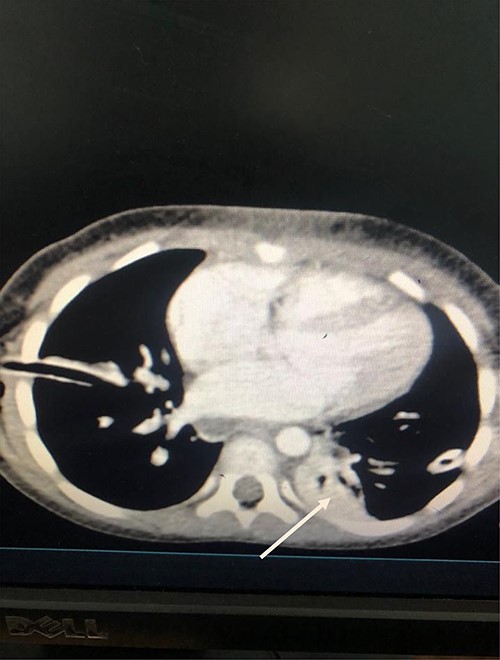

Dissection of the lesion was done with no major damage to the neurovascular or respiratory structures. The thoracic duct was injured, identified and ligated. The patient recovered well post-anesthesia and surgery, and was sent to surgical pediatric ward. At 18 hours post-surgery, she had progressive difficulty breathing, necessitating oxygen support through nasal prongs. Respiratory examination revealed reduced air entry bilaterally. Diagnostic needle thoracostomy was done, and it revealed milk-like fluid bilaterally. Chest tubes inserted bilaterally and drained a total of 250 ml of chyle (150 ml and 100ml), the latter being on the right side (Fig. 2). Drained fluid had higher triglyceride levels (130 mg/dl) than serum levels (80 mg/dl).

She was kept on conservative management with lipid restriction and octreotide. A day later, she had resolved respiratory signs and symptoms. Control computed tomography (CT) revealed significant improvements with minimal fluid on the left side (Fig. 3).

Axial Slice of the thorax showing bilateral thoracostomy tubes and minimal fluid on the left side (white arrow).